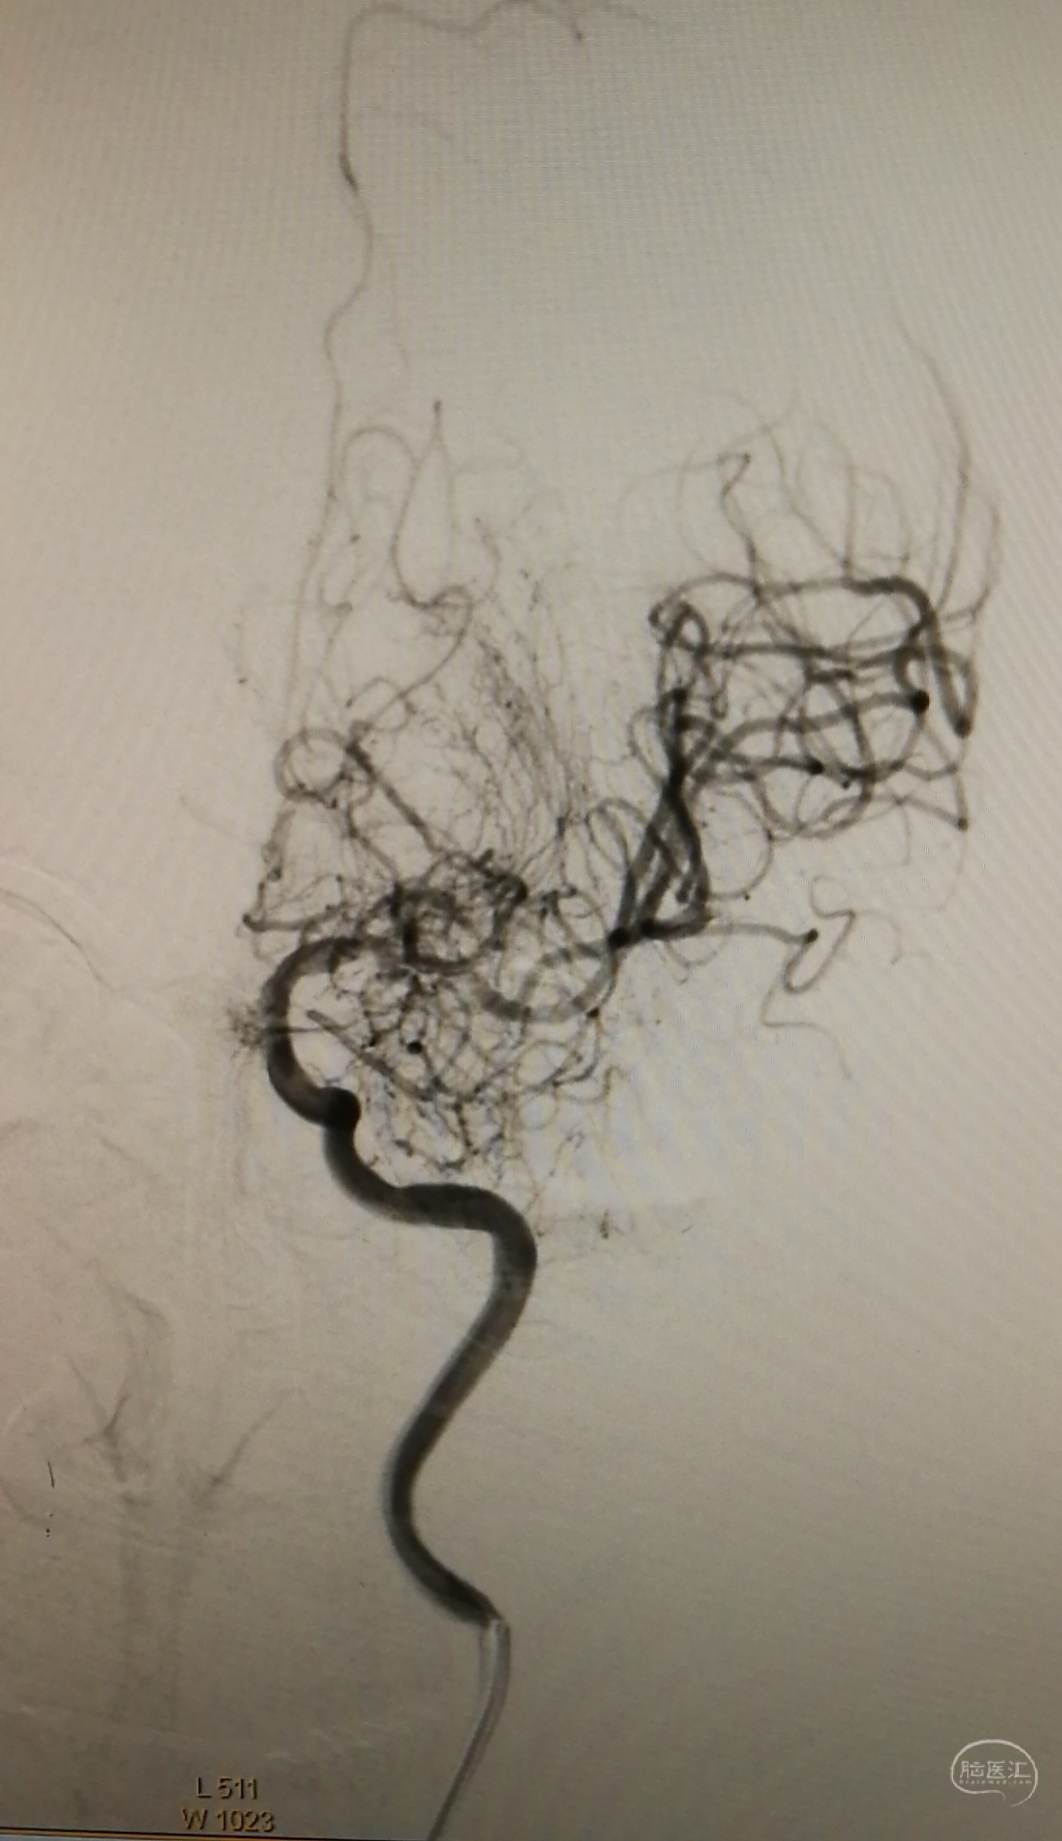

DSA示:左侧大脑中动脉闭塞,烟雾样血管形成。

DSA示颞浅A未向颅内代偿。

DSA示:左侧大脑前、大脑中动脉闭塞,烟雾样血管形成。